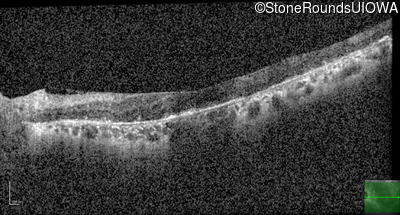

Age at visit: 53 years

OD OS

This 53 year old woman first came to attention when she had difficulty walking down stairs. A few years later she noticed difficulty seeing in dim light.